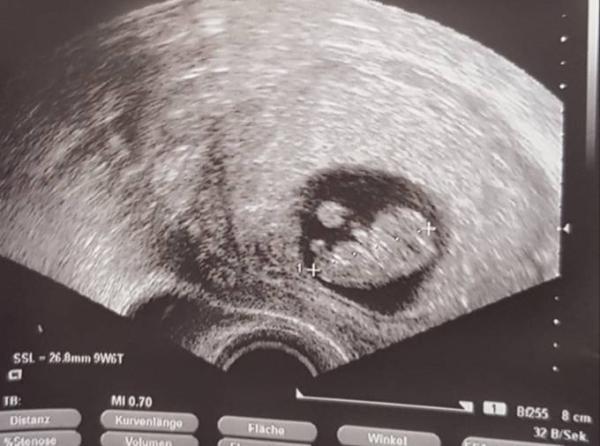

Hallo :) Bei mir lässt die Übelkeit jetzt auch langsam nach (hatte mich schon fast dran gewöhnt:D) Heute habe ich noch nicht gebrochen Gestern war zwar nicht so ein schöner Tag wegen der Übelkeit, aber dann gibts Tage wo es mir echt gut geht. Vielleicht haben wir es ja bald geschafft :) Brüste tun auch nicht mehr weh, sind nur riesig (für meine Verhältnisse :D) geworden. War am Freitag beim Arzt und hab den Krümel mit einem schlagenden Herzchen, Armen und Beinen gesehen Wir sind so verliebt.

Bild zu

Oh was für ein tolles Bild